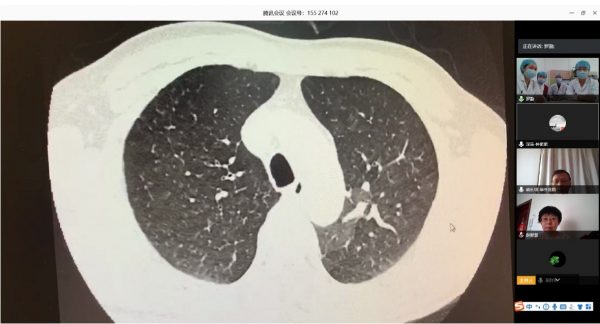

根据卫健委新冠肺炎疫情防控工作总体部署以及医院要求, 3月16日,北阜肺血管与血栓一病区和深阜肺血管病房已同步开始有序收治患者,开展包括右心导管、肺动脉造影及慢性血栓栓塞性肺动脉高压患者的肺动脉球囊扩张术等手术在内的肺血管病所有诊治。为减少新冠肺炎疫情传播风险,保证深圳肺动脉高压患者得到最佳诊疗方案,北阜和深阜两地肺血管病房充分利用“互联网+医疗”的优势作用,开展远程线上查房,对每位患者资料进行详细分析,确定诊治方案,使深圳的患者在疫情特殊时期可得到与平时同样的医疗服务。